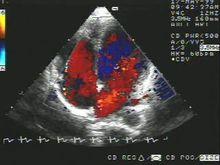

彩色都卜勒超聲心動圖彩色都卜勒超聲心動圖(color Doppler echocardiography,CDE)

它是在二維超聲心動圖定位情況下,利用都卜勒原理,採用一系列電子技術,實時顯示心臟或大血管內某一點一定容積(SV)血流的頻譜圖。是一種無創傷性能檢查出心內分流和返流的技術。連續式都卜勒可連續發射衝波,因此具有測量高速血流的能力,對於定量分析心血管系統中的狹窄、返流和分流性病變,有其明顯的優點。

基本色:紅、綠、藍三種

紅色:朝向探頭

藍色:背向探頭

湍流:綠色

正向湍流:黃色

反向湍流:接近深藍色

作用:實時顯示血流信號的空間信息